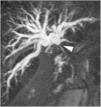

Un varón de 51 años de edad fue evaluado por ictericia obstructiva asociada a una dispepsia leve. El paciente tenía una historia médica regular, y la examinación física no reveló hallazgos significativos salvo por la ictericia. Los resultados de laboratorio mostraron enzimas hepáticas alteradas (bilirrubina total 20.1mg/dl, bilirrubina directa 18.8mg/dl, AST 53U/l, ALT 144U/l, GGT 386U/l y ALP 203U/l). Por medio de una tomografía computarizada (TC) y una subsiguiente colangiopancreatografía por resonancia magnética (CPRM) se demostró la presencia de una masa hiliar de 1.2cm, lo que constituía una estenosis hiliar y oclusión del tracto biliar y dilatación del mismo en el área intrahepática (fig. 1), lo cual sugirió el diagnóstico de colangiocarcinoma hiliar (Bismuth-Corlette II). La colangiografía percutánea para el drenado biliar interno-externo confirmó la contracción hiliar (fig. 2A); una colangiografía realizada 10 días después mostró su normalización (fig. 2B). El paciente se sometió a colangioscopia, confirmando hilio biliar normal (fig. 3), y se tomaron biopsias endobiliares por medio de fórceps en la misma sesión. La evaluación histopatológica reveló infiltrado celular inflamatorio crónico transmural sin signos de malignidad. La tinción inmunohistoquímica mostró células plasmáticas IgG4 positivas (figs. 4A y B). Seis meses después se confirmó un árbol biliar normal por medio de una CPRM (fig. 5).